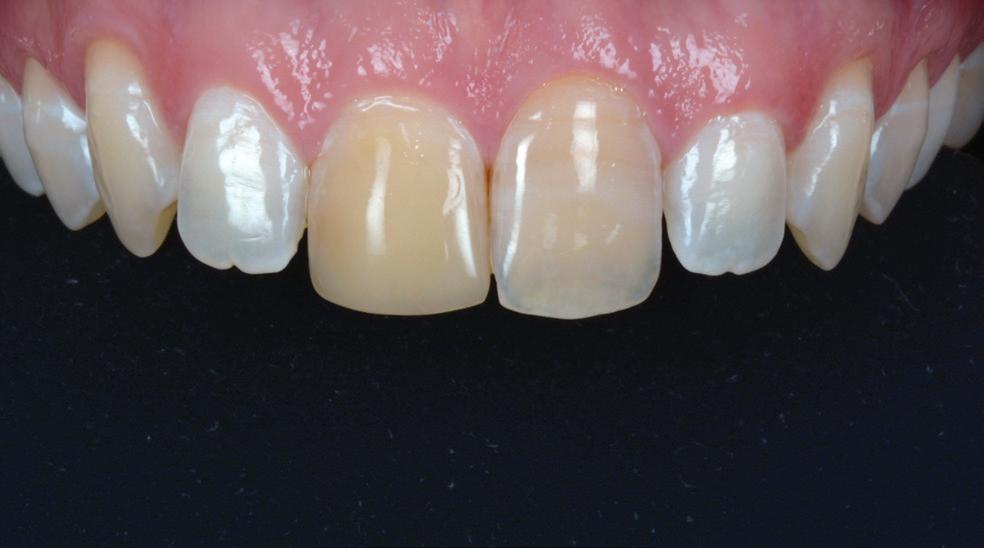

Seamless integration with new DTX Studio™ Clinic software

P acked with AI-assisted software features, DTX Studio™ Clinic complements OP 3D LX in numerous ways—for example, correcting patient positioning errors and detecting

landmarks, annotating mandibular nerve canals, tracing patientspecific panoramic curves for mandible and maxilla and merging CBCT and intraoral scan data for improved implant planning. These intuitive award-winning software features support a more efficient workflow allowing you to spend less time in the software and more time with your patient.